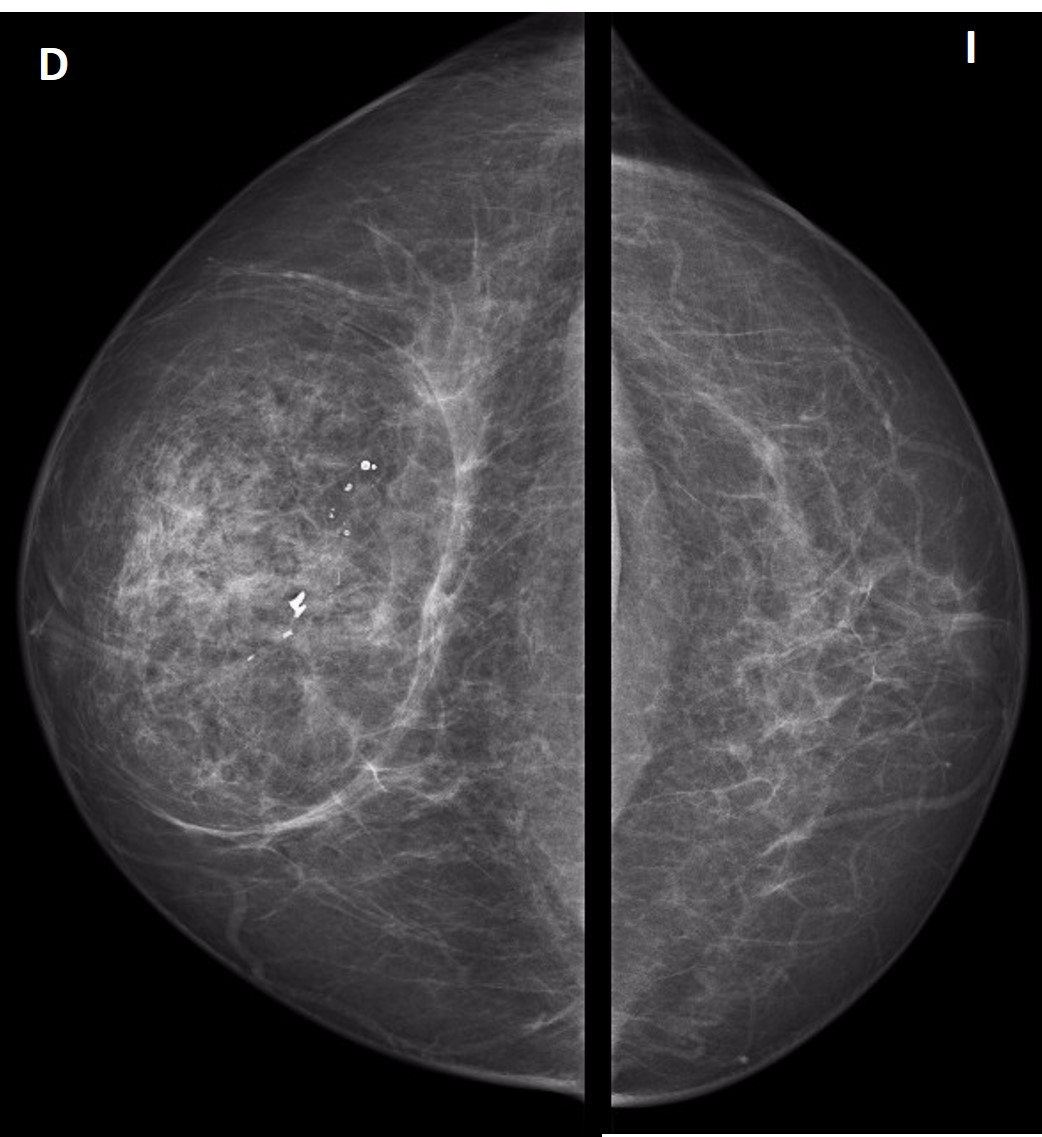

Hamartoma. a En la mamografía se observa en el cuadrante externo una ... 😈